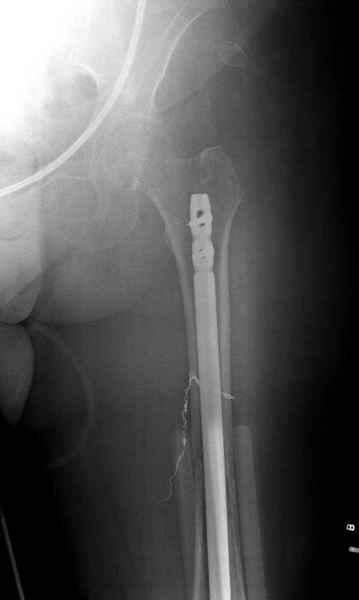

Патологический перелом бедра, конечность на вытяжении.

Известно, что многие из нас независимо от метода лечения и стадии первичной опухоли проводят интрамедуллярное штифтование при различных патологических состояниях бедра, включая патологические переломы.

Для предупреждения кровотечения во время рассверливания, за день до операции провели эмболизацию сосудов питающий метастаз. http://radiology.rsnajnls.org/cgi/reprint/150/3/673.pdf (7-11, 12-15-16)

С минимальным рассверливанием и ретроградным методом провели остеосинтез бедра 12 мм гвоздем. (17-20)

Кровопотеря во время операции меньше 100 мл.